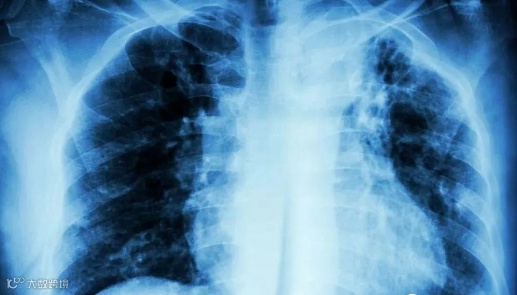

肺纤维化是以成纤维细胞增殖及大量细胞外基质沉积、肺组织结构破坏为特征的间质性肺疾病的终末期肺脏改变。

表现为干咳、进行性加重的呼吸困难,轻度肺纤维化通常在剧烈活动时出现。当肺纤维化进展时,在静息时也发生呼吸困难,严重者会出现进行性呼吸困难、发绀。